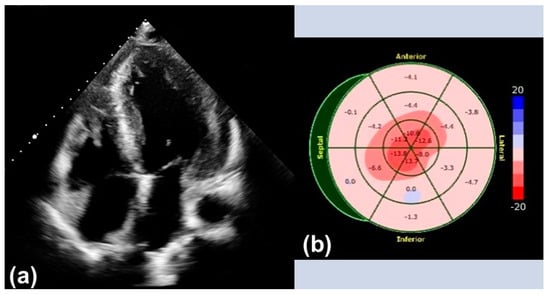

Transthoracic echocardiography (TTE) is widely available and can be performed in any setting, making it an excellent screening tool for initial evaluation. Increased thickening of the left ventricular wall, the interatrial septum, as well as the valves, and the presence of pericardial effusion are typical findings suggestive of CA (Figure 1). In addition, the assessment of diastolic function, which is usually impaired (Grade 2 or more), is of great importance and only feasible with TTE [7].

Strain evaluated by speckle tracking echocardiography (STE) presents an additional feature in the diagnosis of CA. A ‘speckle’ of myocardium identified by software is followed through a cardiac cycle to reveal information on its radial, longitudinal, and circumferential deformation. Therefore, a certain degree of image quality is necessary for conduction of STE. The characteristic STE pattern shows a reduction in global longitudinal strain (GLS) of the left ventricle in the basal and mid-ventricular segments with an apical sparing also called the ‘cherry-on-top’ sign and preserved left ventricular ejection fraction (LVEF).

Figure 1. Typical findings in transthoracic echocardiography: (a) Apical four-chamber view with left ventricular hypertrophy. (b) Echocardiographic strain imaging with ‘cherry-on-top’ sign.